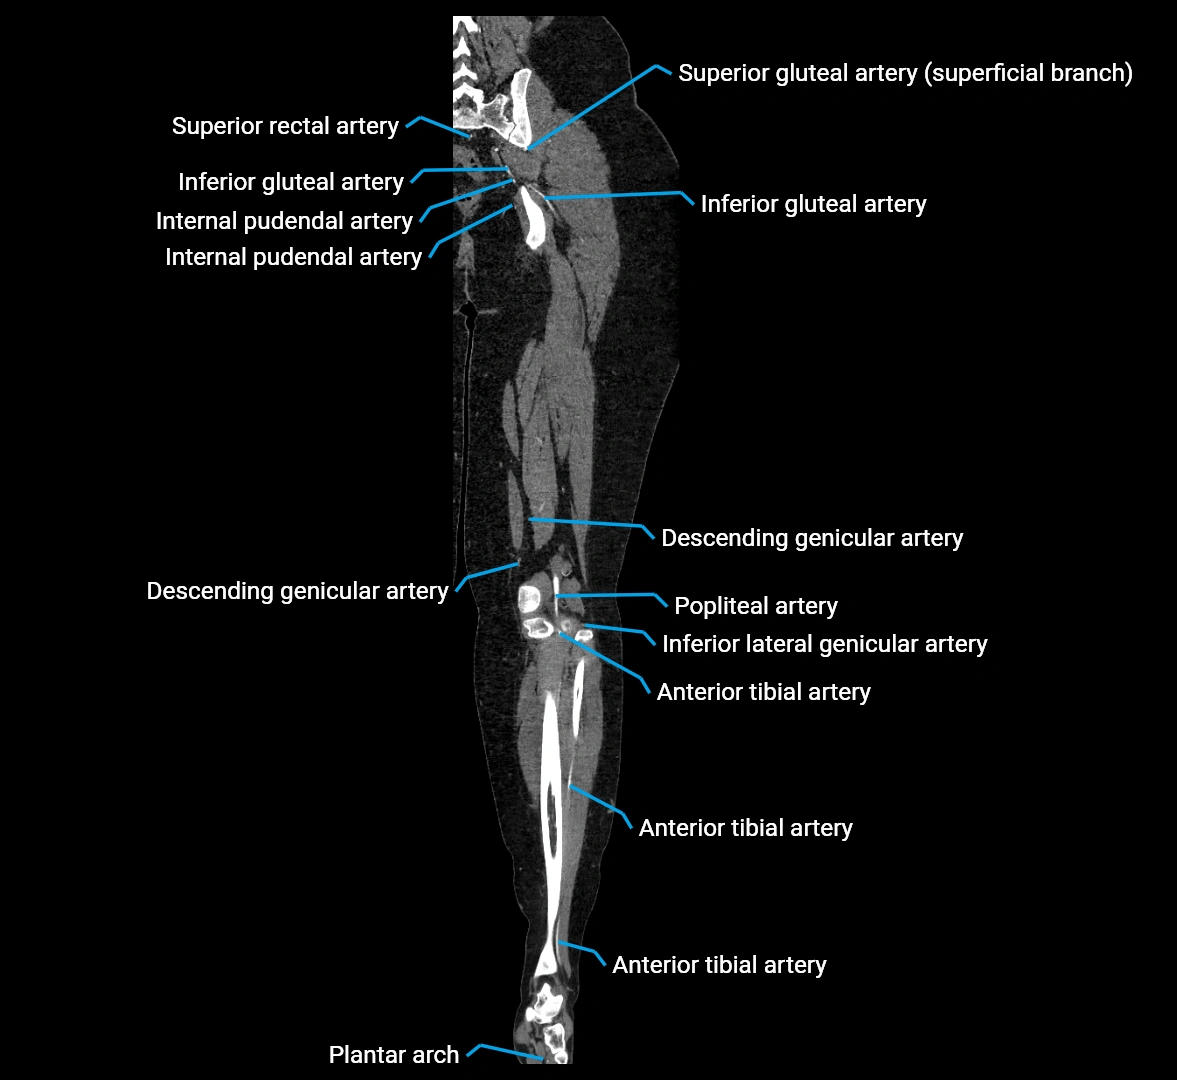

CT images

image